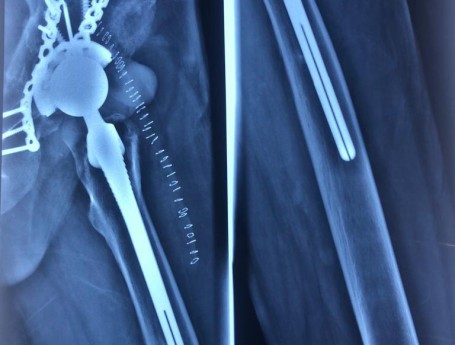

Revision Total Hip Arthroplasty Femoral Stem